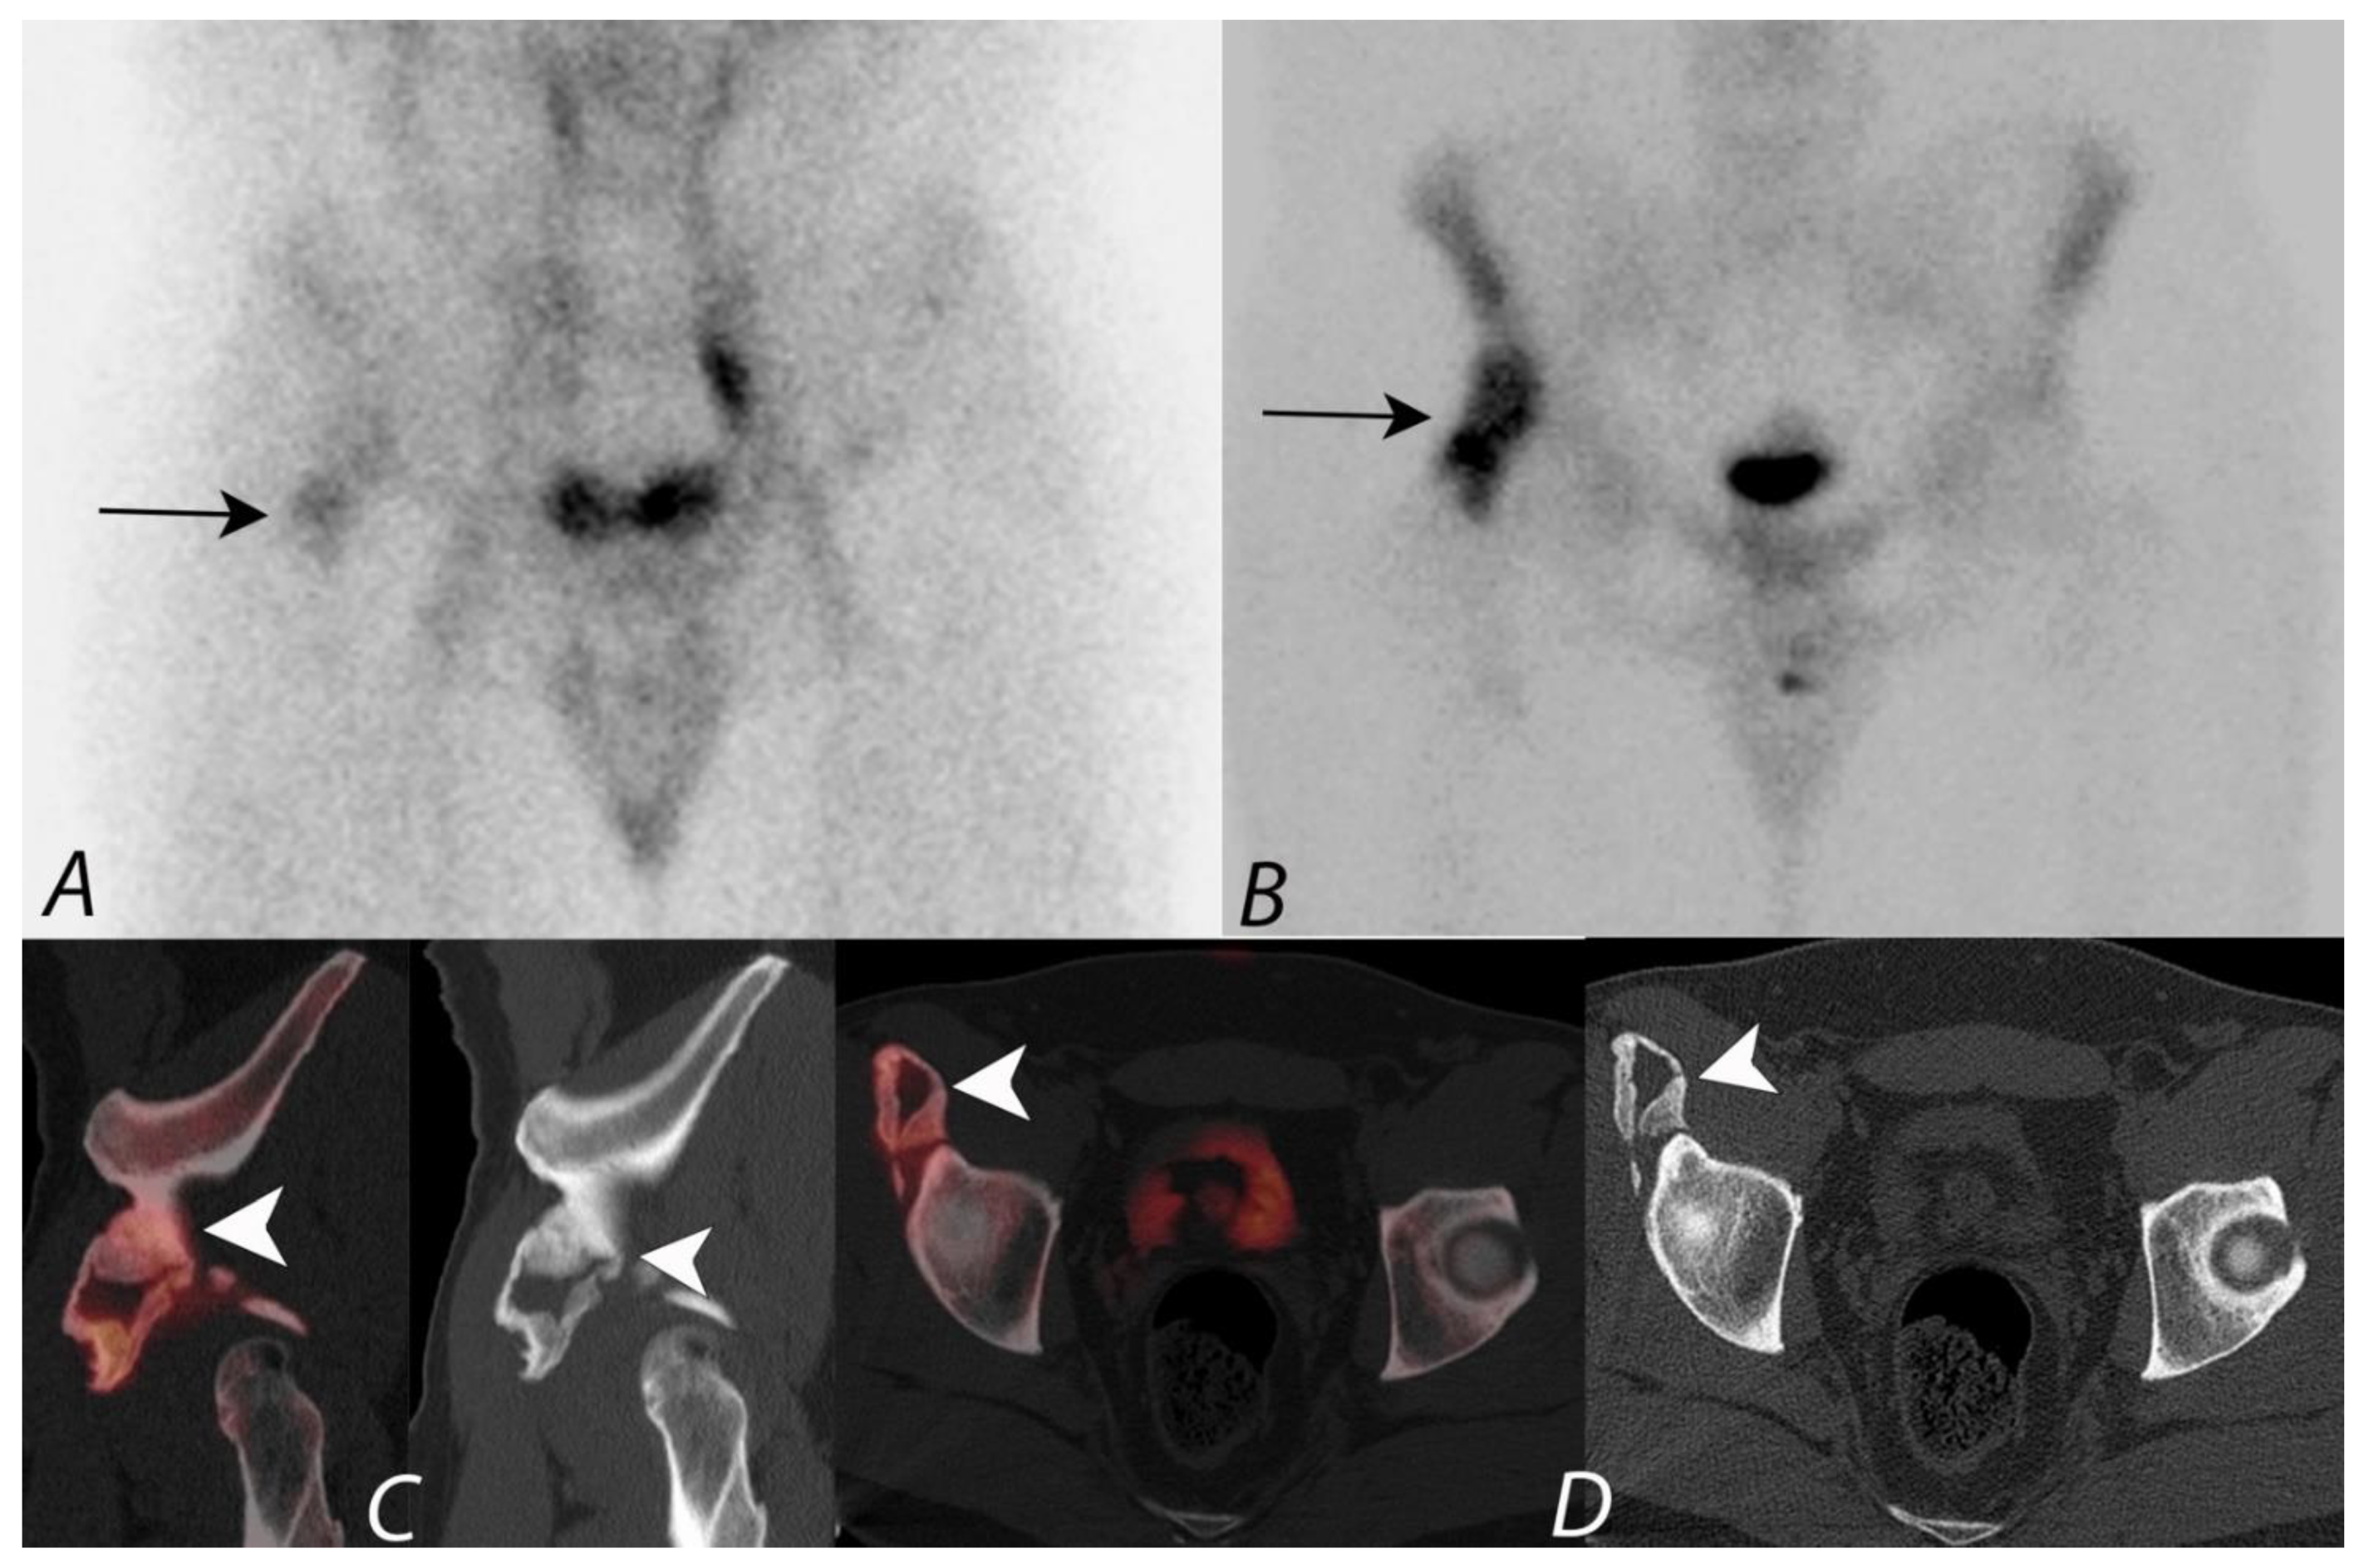

Figure 3.

Anterior and posterior whole body 99mTc MDP bone scan planar images (A) from a Tc-99m MDP bone scan in a 68-year-old male with prostate cancer and new pelvic pain demonstrate focal uptake (black arrows) localizing to the left sacral region. Coronal CT and fused SPECT/CT images (B,C) demonstrate the uptake localizing to a vertical insufficiency fracture of the left sacral ala, which demonstrates osteoblastic activity, confirming a healing insufficiency fracture and not metastatic disease.